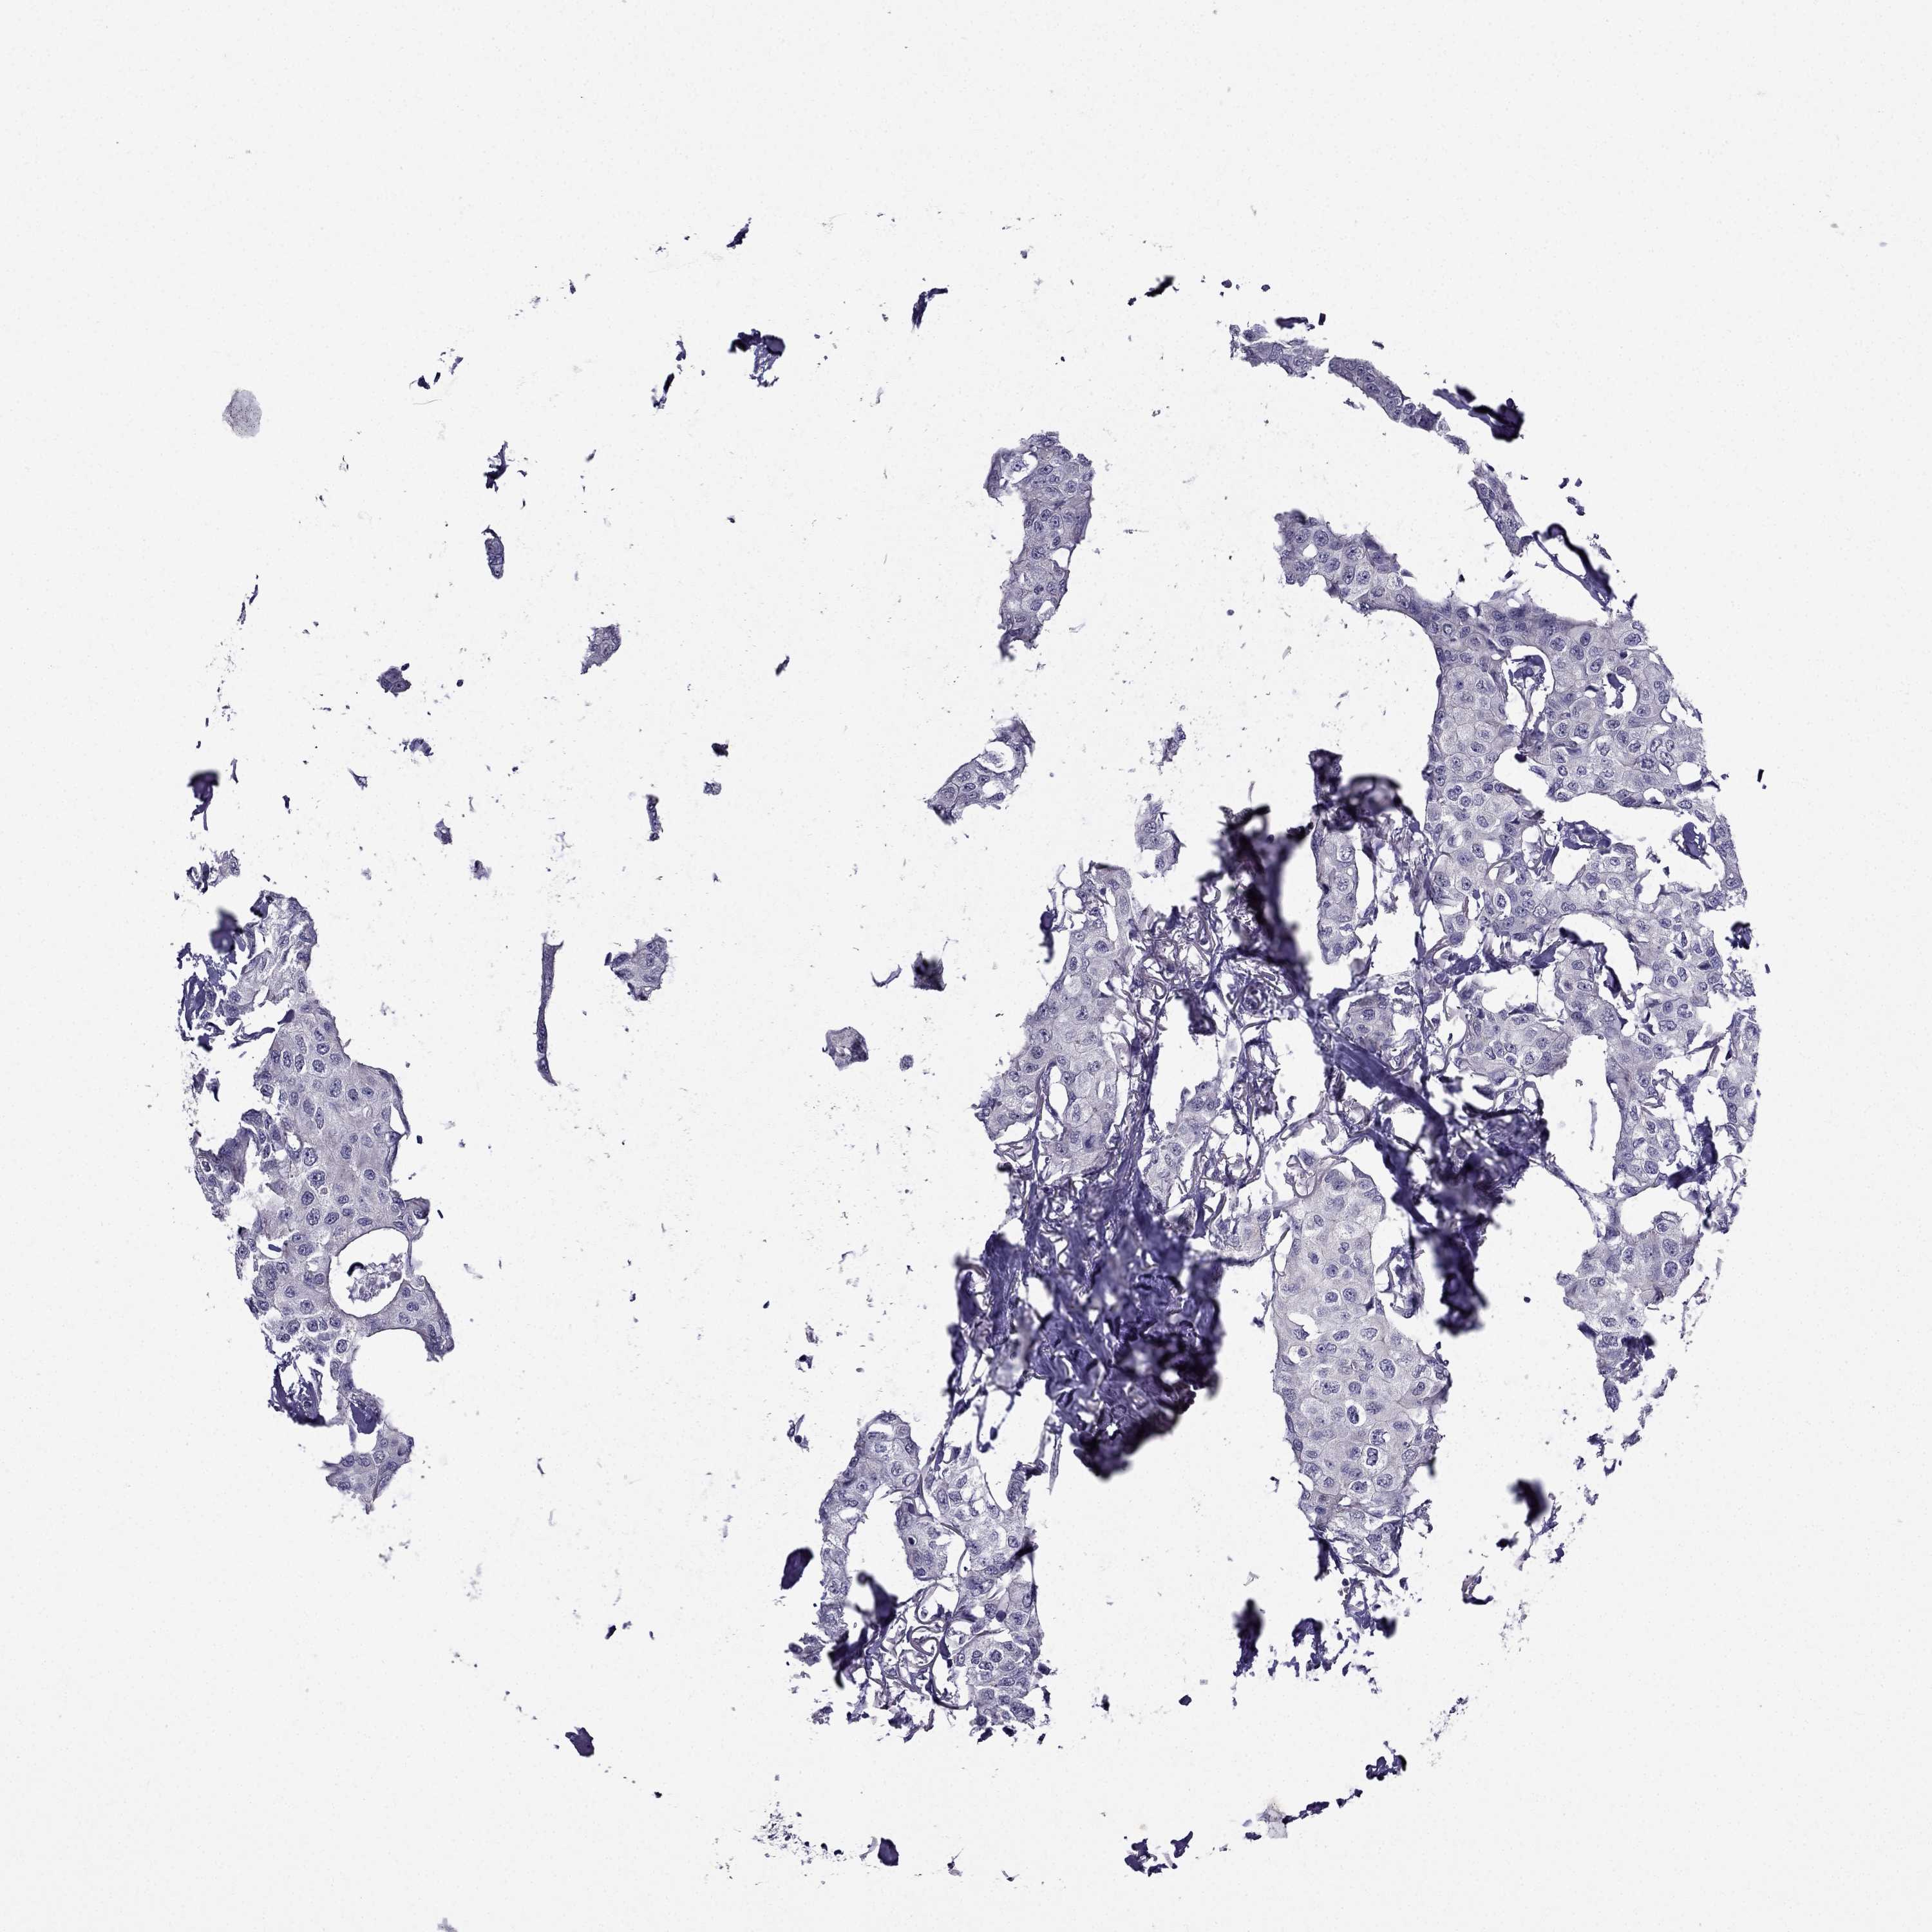

Breast cancer

Human cancer